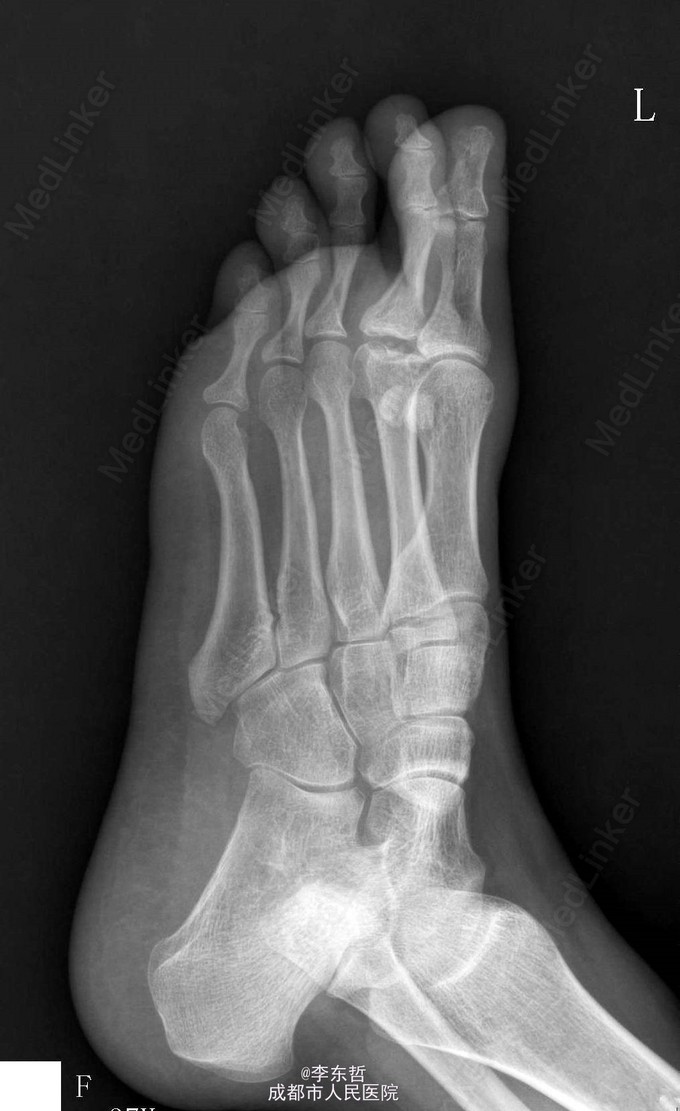

第二跖骨坏死

患者青年女性,因脚底疼痛2月加重3天来院就诊,入院后x线片出现“骨端烟头征”:软骨坏死的X线征之一,正常关节面变模糊,表面参差不齐,如燃烧的烟头样;提示第二跖骨头坏死迹象。